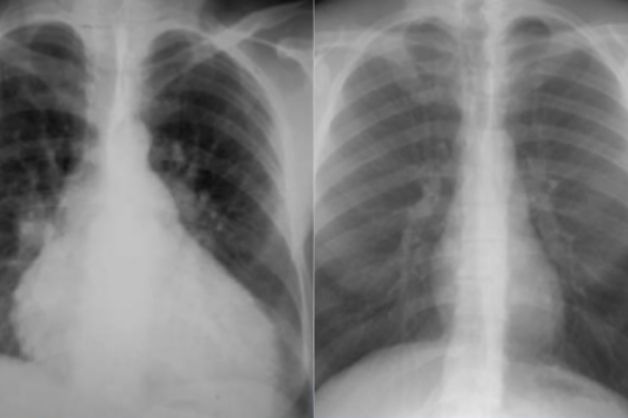

X quang tim được xem là kỹ thuật quan trọng giúp đánh giá và xác định kích thước bóng tim. Thông qua các chỉ số tim và lồng ngực, các bác sĩ chẩn đoán hình ảnh sẽ có kết luận bóng tim to hay nhỏ ở mỗi trường hợp bệnh nhân.

Chỉ số này thể hiện tỉ lệ giữa kích thước chiều ngang lớn nhất của bóng tim với kích thích chiều ngang lớn nhất của lồng ngực. Khi chỉ số tim, ngực trên kết quả X quang tim thay đổi sẽ gợi ý một số chẩn đoán sau:

– Chỉ số tim lồng ngực > 0,55: tình trạng tim to, thường gặp trong các bệnh lý về cơ tim, suy tim, van tim bất thường, tràn dịch màng ngoài tim…

– Chỉ số tim lồng ngực

Phân tích kích thước buồng tim là một trong các vấn đề cần lưu ý khi phân tích phim X quang tim